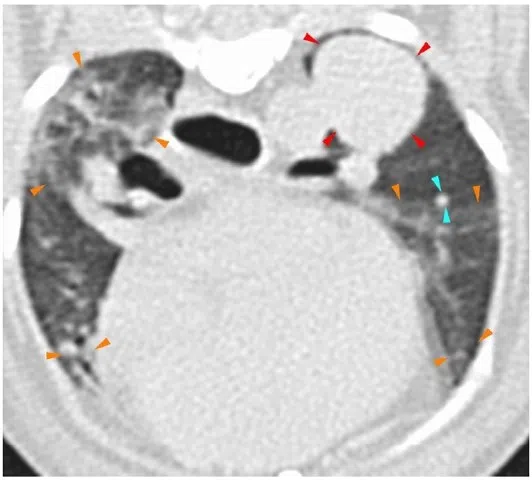

A scan of Oscar’s lung, showing the 1.5cm tumour in his left lung.

PHOTO: NUS YONG LOO LIN SCHOOL OF MEDICINE

Further tests revealed a 1.5cm tumour lodged in Oscar’s left lung. Canine lung cancer is rare but deadly, and the 11-year-old poodle was given only three months to live.

Oscar underwent five treatment cycles between March and September 2020, which were free, as they were part of a trial. He did not experience many side effects except for feeling lethargic and being less active, said his owner.

The dog had eight more treatment cycles ending in May 2022, when the tumour was found to have grown. Since then, it has shrunk slightly and has remained at 1.7cm. Oscar is now 14 and lives a normal life, with less frequent coughing and some asthma.

The tumour stayed at 1.7cm after Oscar underwent additional rounds of treatment.

Dr Lee, Oscar’s vet, said: “That was one of the best outcomes we could expect from a lung tumour because it is typically quite aggressive and fast-growing.”